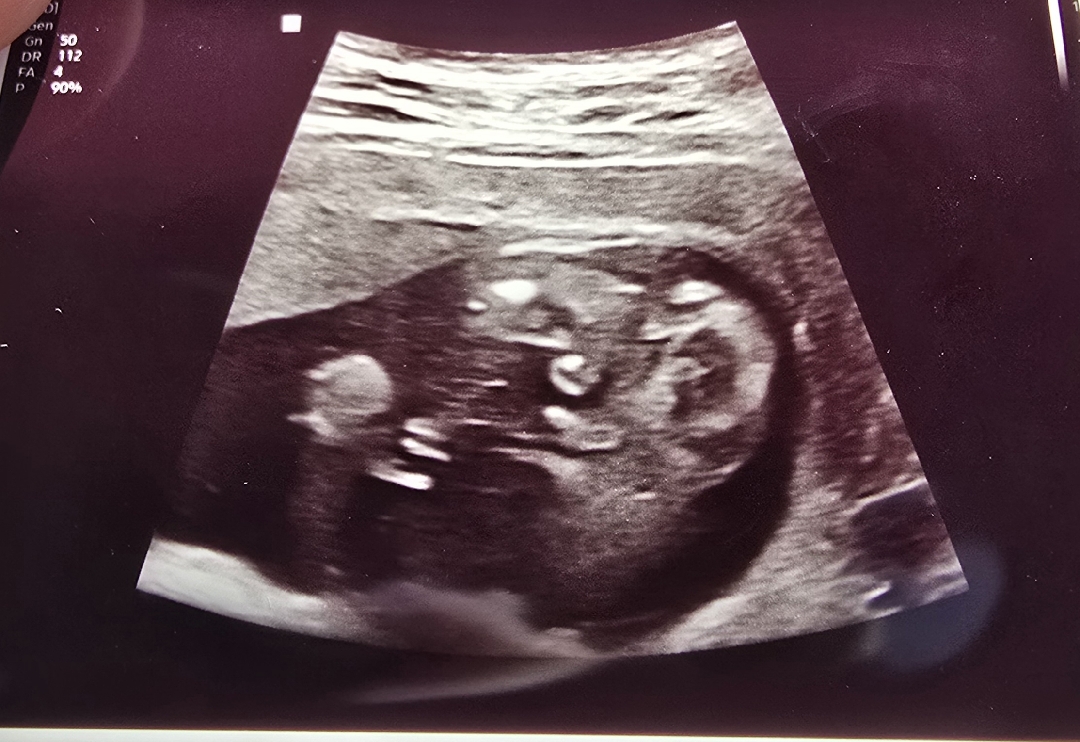

[16주 1일] 자꾸 움직여서 담에 또 보자시는데ㅜㅜ

16주 1일차 병원 갔다가 집에 가는길인데 자꾸 움직여서 탯줄인지 아닌지 다음 진료때 다시 보자 하시는데ㅜㅜ 저 너무 궁금했거든요ㅜㅜ 딸이 셋이라ㅎㅎ 막둥이 넷째는 아들이였음 했거든요! 아들일것 같긴 한데..라고 하셨는데 고수님들 한번 봐주세요~~~ 저거 탯줄일까요?ㅜㅜ